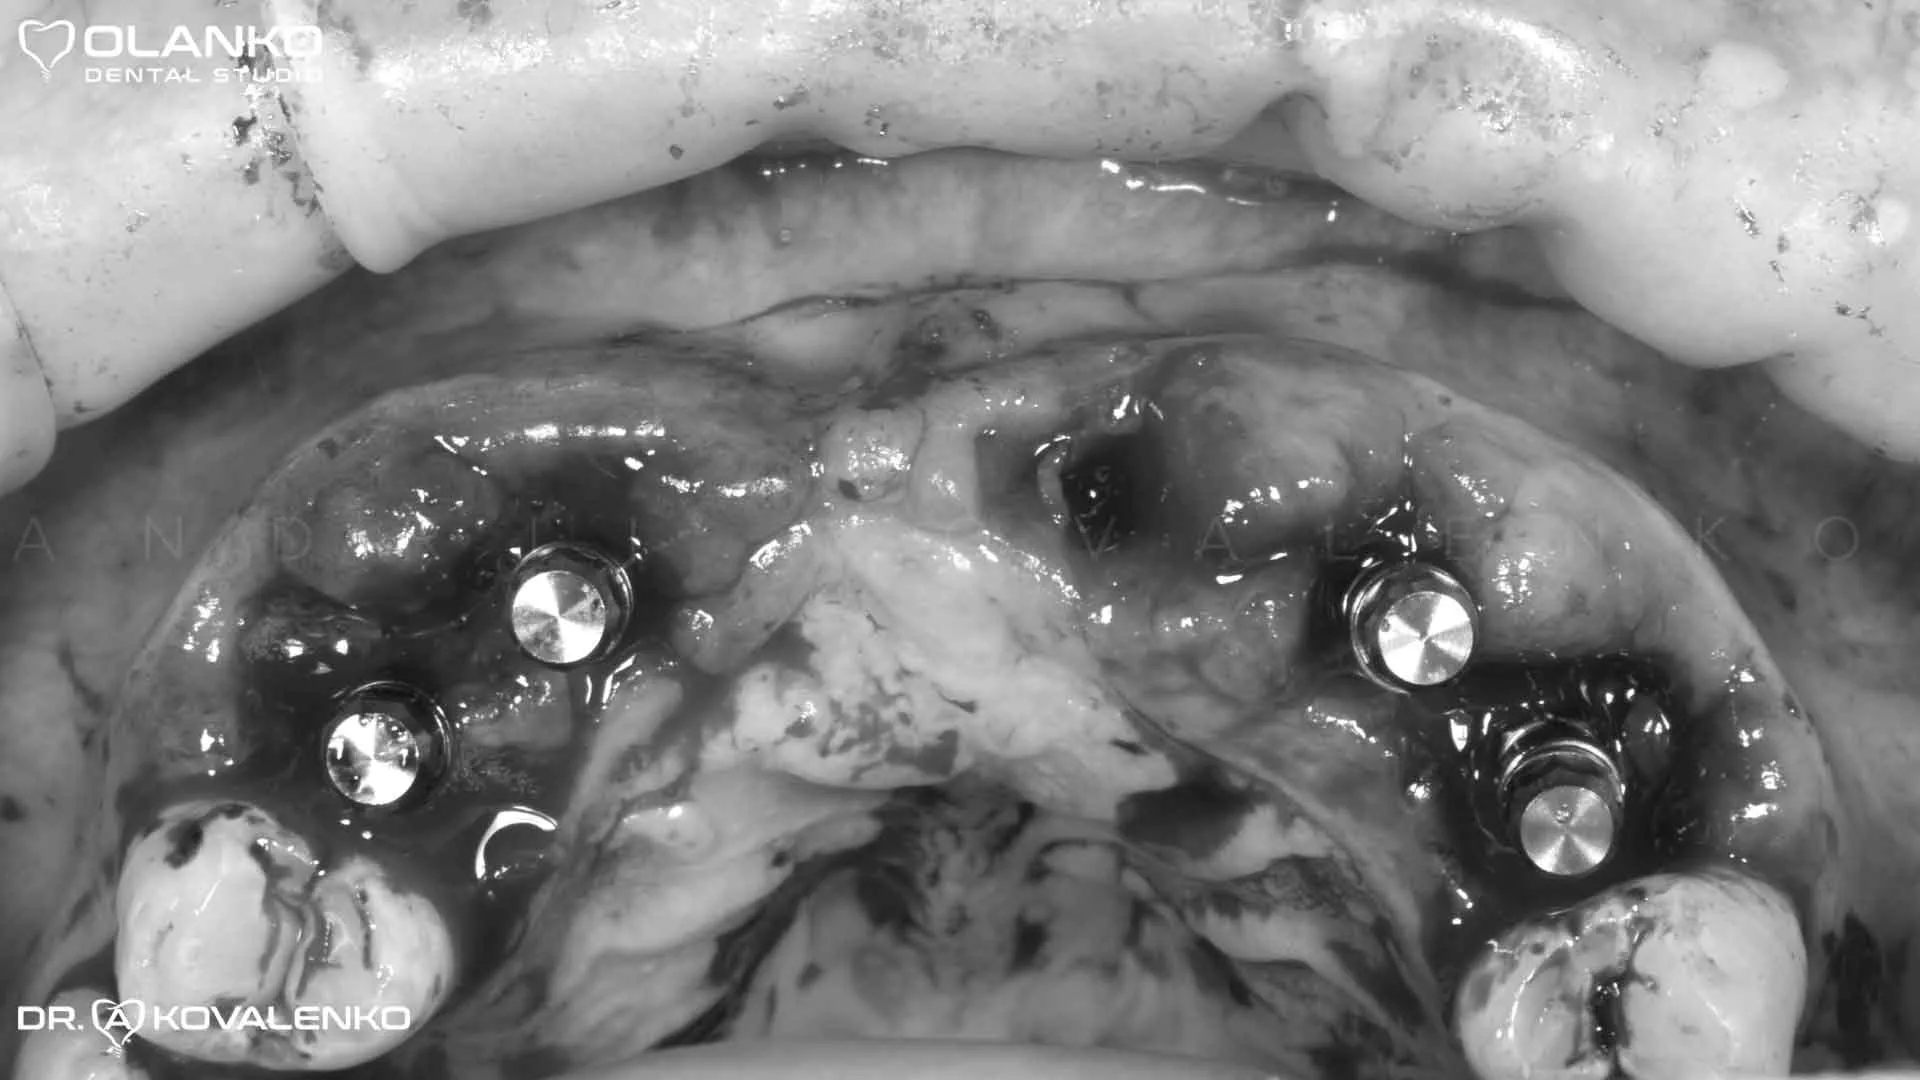

Фото вигляд зруйнованих зубів після зняття металокерамічного мосту

Фото момент установки зубних імплантатів